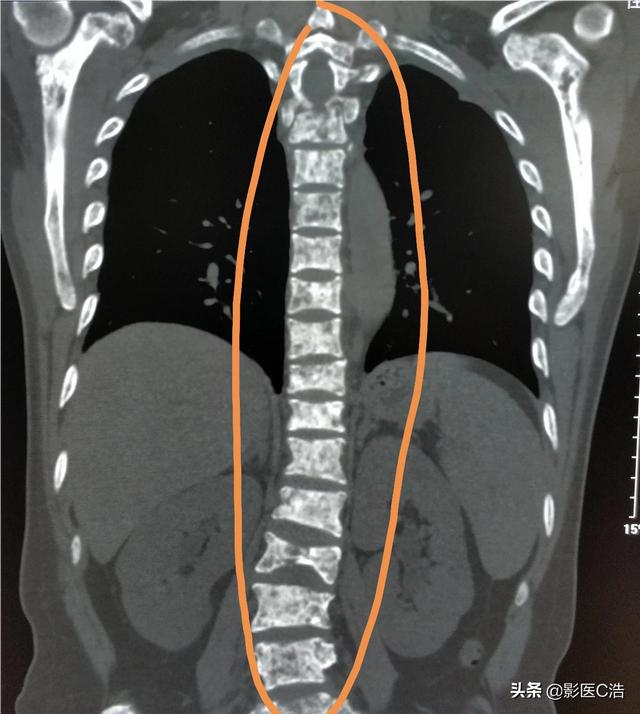

Welche Art von Schmerzen sollten auf eine Knochenmetastase hinweisen? Knochenmetastasen sind eine häufige Erscheinung bei bösartigen Tumoren im Spätstadium, d. h. der Primärtumor ist über Blut- und Lymphbahnen in andere Körperteile eingedrungen und hat dort Knochenmetastasen gebildet. Knochenmetastasen bedeuten, dass normales Knochengewebe zerstört und durch Tumorgewebe ersetzt worden ist. Knochenmetastasen lassen sich je nach Spezifität der Läsion in drei Typen einteilen: osteolytischer Typ, osteogener Typ und Mischtyp. Die häufigsten Stellen, an denen Knochenmetastasen auftreten, sind der mittlere Schaftknochen (Wirbelsäule und Becken), die Rippen und die untere Metaphyse, wobei vor allem der mittlere Schaftknochen am häufigsten betroffen ist, was mit den Eigenschaften der Blutversorgung in diesem Bereich zusammenhängt. Wie im Kreis unten dargestellt, gibt es mehrere Knochenmetastasen und die Wirbelsäule ist in einem schlechten Zustand.

Gerade vor ein paar Tagen nur einen Fall von Lungenkrebs Knochenmetastasen Patienten diagnostiziert, ist sein Symptom langfristige lumbale Rückenschmerzen, haben sie immer gedacht, dass es lumbale Muskelzerrung ist, oder von lumbalen Bandscheibenvorfall leiden, kümmerte sich nicht, wirklich der Schmerz ist ernst, und erschien die Nervensymptome der unteren Gliedmaßen, nur in das Krankenhaus für die Prüfung, gegeben, um seine CT-Untersuchung, festgestellt, dass es offensichtlich Wirbelknochen Zerstörung sind ...... detaillierte Verfolgung der Krankengeschichte, festgestellt, dass der Patient seit langem Hustensymptome hat, so hoch Verdacht auf Lungenkrebs Knochenmetastasen, die Lunge CT-Untersuchung, fand der primäre Fokus ...... eine große Lungenkrebs.